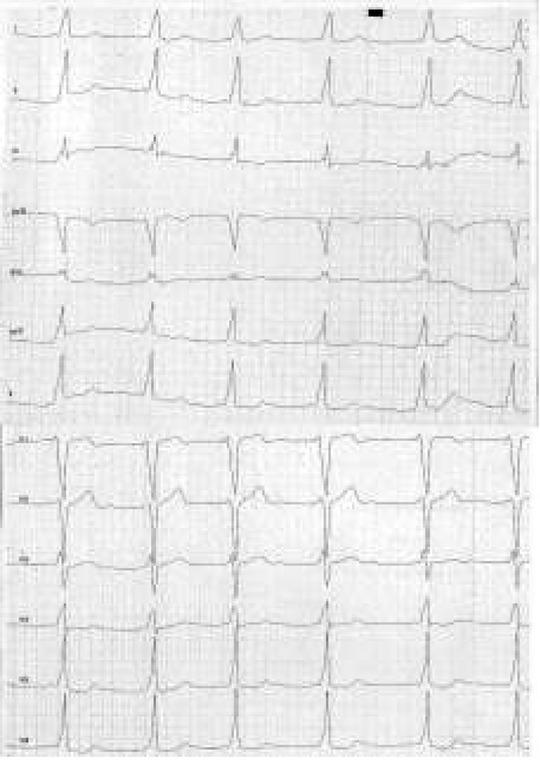

Fig. 5

ECG of a 9-year-old patient with orthodromic atrioventricular recurrent tachycardia. Heart Rate = 240 bpm [own material].

Ryc. 5. EKG 9-letniego pacjenta z ortodromowym nawrotnym częstoskurczem przedsionkowo-komorowym. Rytm serca o częstości 240/min [materiał własny].